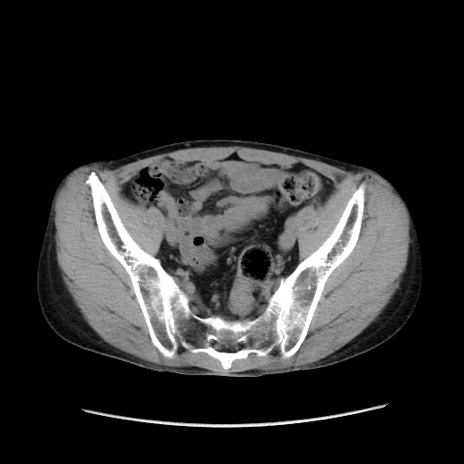

症例37(横断像)

【症例】40歳代 男性

【主訴】腹痛

【現病歴】4時間ほど前に電車に乗車中に臍部上より腹痛出現。徐々に増悪し起立困難となり、救急外来受診。生ものは数日食べていない。今朝お雑煮を食べた。

【身体所見】BT 36.8℃、BP 117/84mmHg、HR 91/min、SpO2 97%、苦悶様、腹部:臍上部広範囲圧痛あり、反跳痛±

【データ】WBC 8100、CRP 0.03